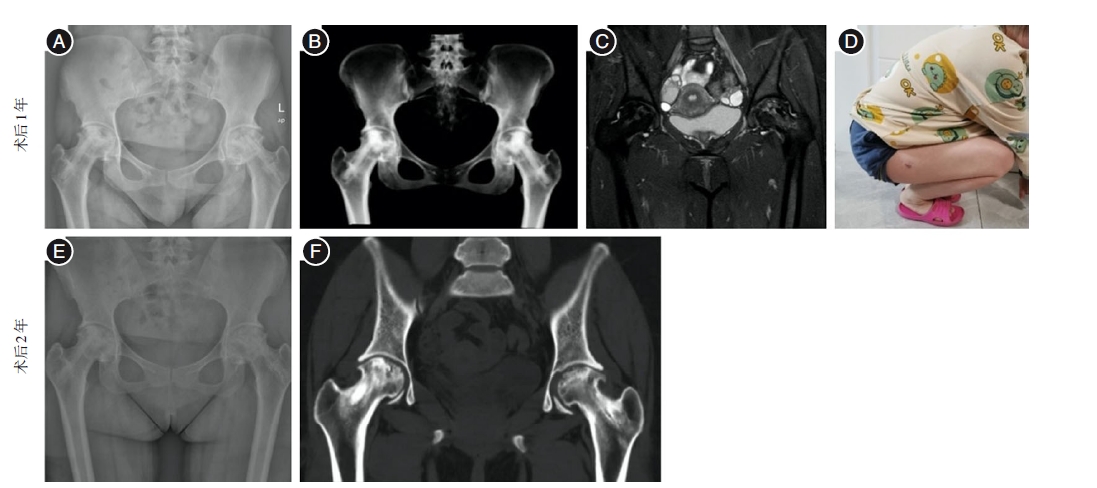

Core decompression combined with BMP activity inducing rod implantation for early femoral head necrosis

Objective To investigate the effect of core decompression combined with bone-morphogenetic proteins (BMP) activity inducing rod implantation in the treatment of early-stage femoral head necrosis. Methods Retrospective analysis of 116 patients with early-stage femoral head necrosis from June 2018 to June 2022 were divided into core decompression combined with BMP activity inducing rod group (BMP group) and allograft bone group. Sixty cases in the BMP group were treated with core decompression combined with implantation of BMP-activated induced rods, and 56 cases in the allograft group were treated with core decompression combined with bone grafting of the allograft bone by punching and compression.The differences in hip Harris scores and visual analogue scores (VAS) of pain between the two groups at preoperative, 6 months postoperative and 1 year postoperative, and the patient treatment response and femoral head survival rate at 1 year postoperative were compared. Results All patients were followed-up, and the difference between the preoperative VAS score and Harris score of the two groups was not statistically significant (P > 0.05), and the VAS score and Harris score of the two groups were significantly improved at 6 months and 1 year after operation, and the BMP group was better than the allograft bone group, with significant difference(P < 0.05). At 1 year after surgery, the Harris hip score excellence rate of the BMP group was higher than that of the allograft bone group, and the difference was statistically significant (P < 0.05); the femoral head survival rate of the BMP group was higher than that of the allograft bone group, and the difference was statistically significant (P < 0.05). Conclusions Core decompression combined with BMP activity induced rod implantation was effective in the treatment of early femoral head necrosis, which accelerated the induction of new bone formation, improved the quality of new bone, provided biomechanical support for the femoral head, and effectively avoided femoral head collapse. Moreover, it has good biocompatibility and couldbe degraded and absorbed in the body, which is worthy of clinical promotion.